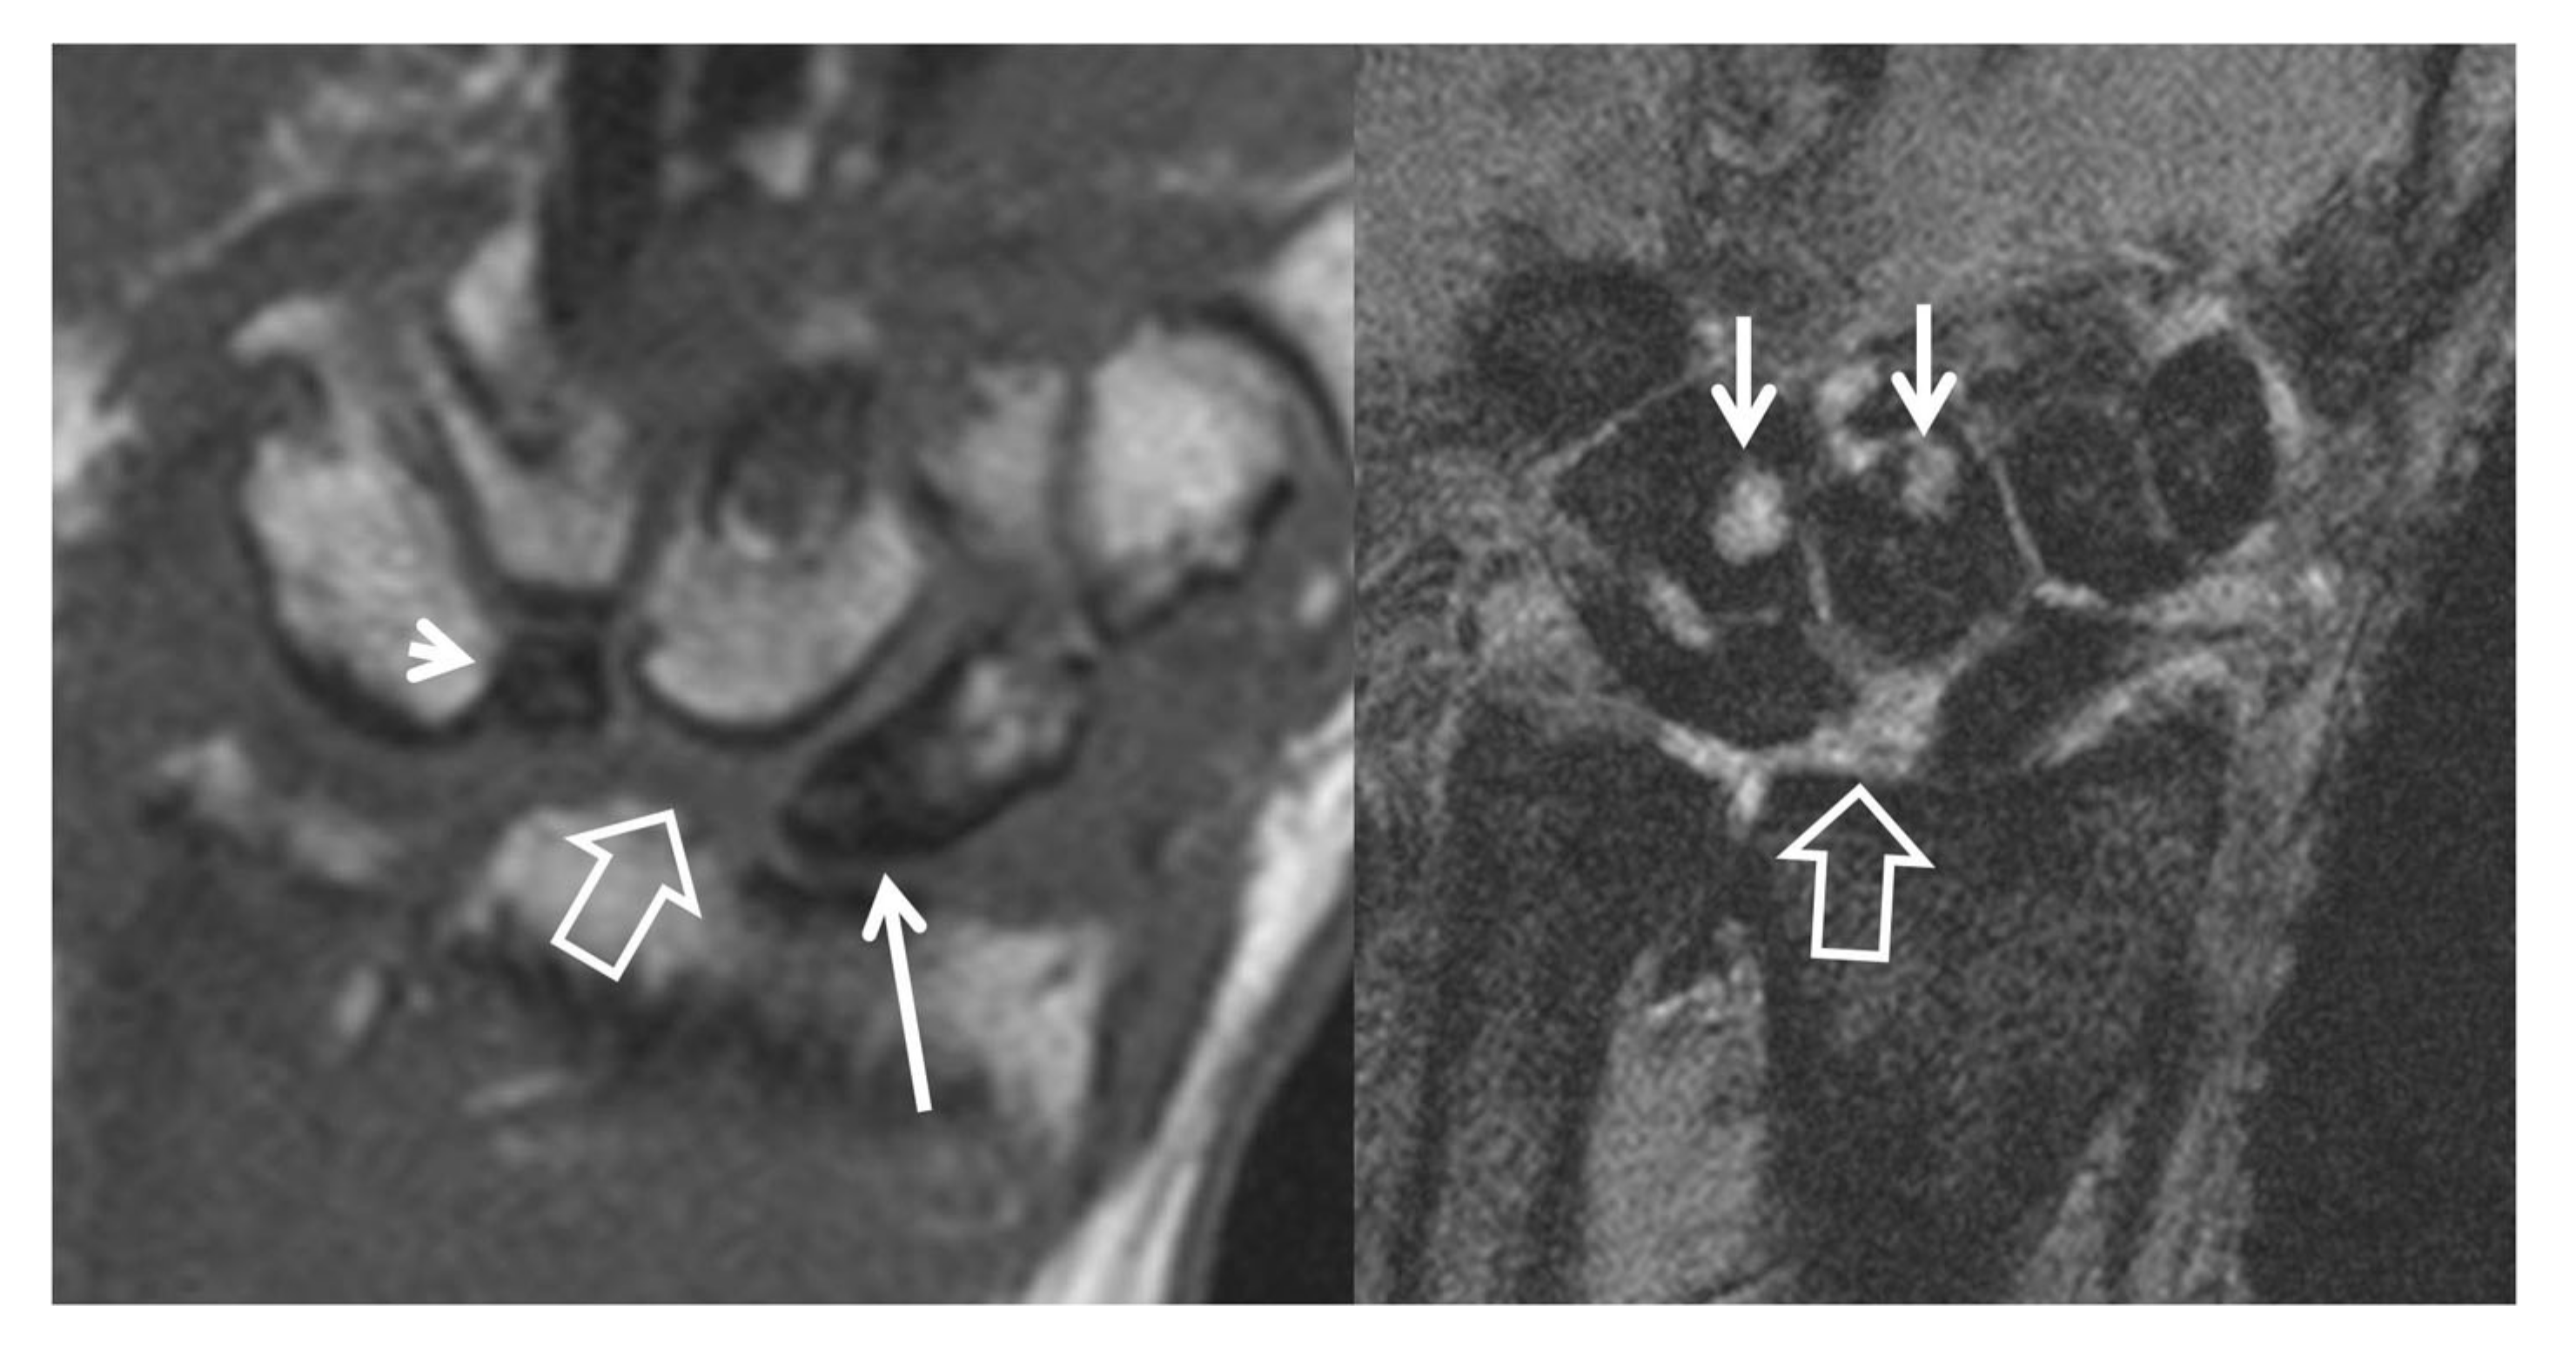

Figure 10.

A 56-year-old male patient with SLAC and SNAC wrist. Coronal T1w (left) and T2* (right) MR images, showing the proximal pole scaphoid necrosis (arrow), the scapholunate diastasis with proximal capitate bone migration (open arrow), the rotation of the lunate bone (arrowhead) and the subchondral cysts secondary to osteoarthritis development (short arrows).